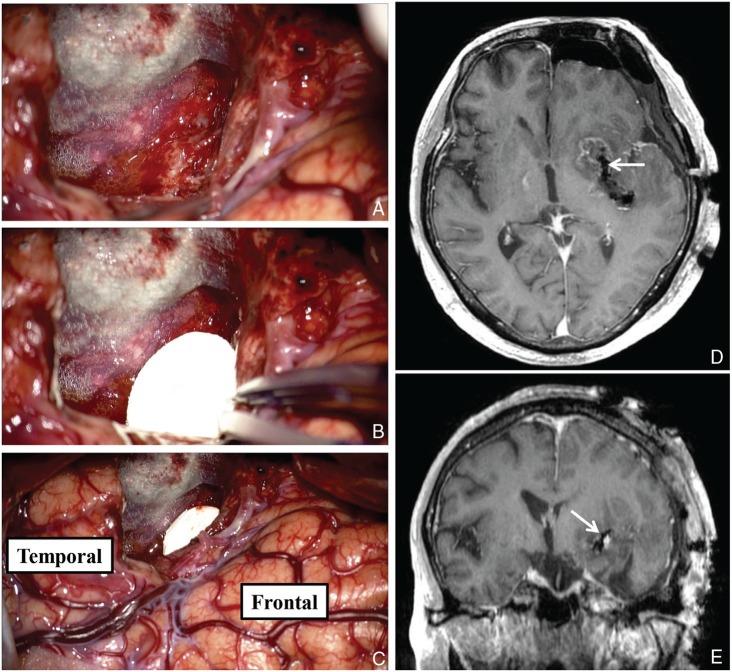

Implantation of carmustine-impregnated wafers (Gliadel) into the tumor resection cavity has demonstrated a survival benefit for patients with malignant glioma. However, some precautions should be taken regarding Gliadel implantation. We report a case of a 63-year-old man with glioblastoma who was implanted with Gliadel after a left temporal lobe tumor had been removed, and who later developed vasospasm of the lenticulostriate artery close to the implanted Gliadel, leading to serious cerebral infarction. Therefore, the implantation of Gliadel in cases where important vessels run close to the resection cavity should be considered with great caution.